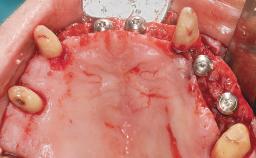

Immediate Loading of Six Implants in the Maxilla and Final Restoration with a Full-Arch CAD/CAM Zirconia FDP

A 63-year-old male patient was referred for a consultation and treatment of partial edentulism in the maxilla. The patient presented with residual anterior teeth and declined a partial removable prosthesis. He reported that the maxillary posterior teeth had been extracted due to mobility and periodontal disease two months before the consultation. The patient’s chief complaint was that his residual maxillary teeth were mobile and that he was unable to chew. The patient’s desire was a stable and comfortable fixed maxillary rehabilitation. The patient was a light smoker (fewer than 10 cigarettes/ day), and his medical history was without significant findings. He was not on any regular medication at the time of consultation. The extraoral examination revealed a normal physiognomy with a correct distribution of the facial thirds. The patient presented a low lip line, and the transition line between teeth and soft tissues was not exposed during a forced smile.

Defining Characteristics Fully edentulous upper jaw to be rehabilitated with four or more implants

Modality 6+ implants with immediate loading